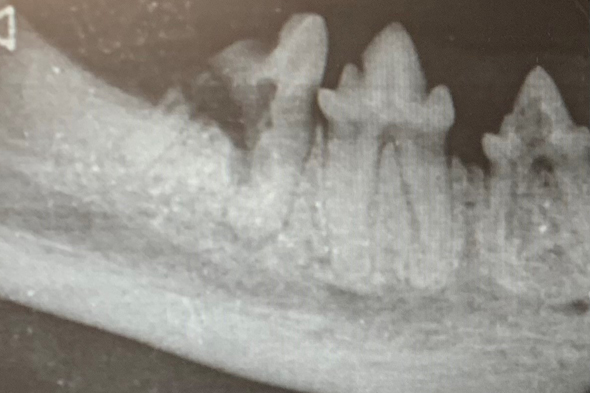

FORL - Resorptive Läsion bei der Katze

Diese Erkrankung tritt bei fast 70 % aller Katzen auf. Dabei führt ein Abbau der Zahnsubstanz zu massiven Substanzverlusten am Zahn, bis die Zahnkrone von der Wurzel abbricht. Das führt natürlich zum Zahnverlust, allerdings verbleiben die Wurzelreste im Kiefer und schmerzen weiter.

Leider werden nur wenige von dieser Krankheit befallenen Katzen erkannt, weil eine genaue Diagnose nur nach einem Zahnröntgen gestellt werden kann. Wichtig für die Behandlung und das Management dieser Erkrankung ist, dass das Ausmaß und die regelmäßige röntgenologische Kontrolle aller Zähne erfolgt.